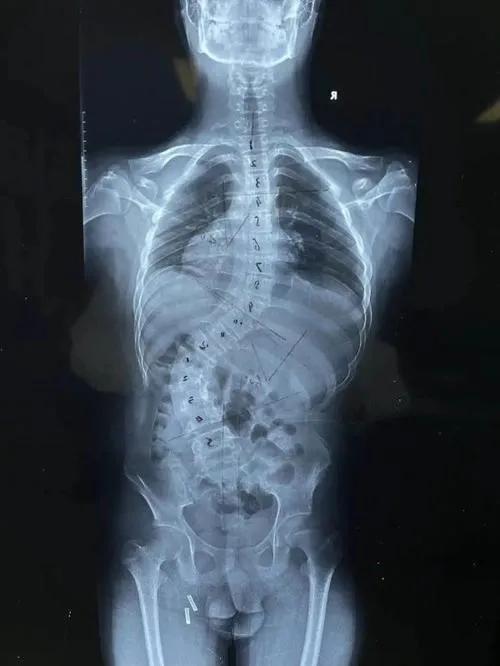

14岁女生,脊柱侧凸,家长发现高低肩后就诊

正常的脊柱,正面看从上到下,是成一直线的,从侧面看,是成“S”形的。而脊柱侧弯的青少年,他们的脊柱却偏离中线,成了拧麻花状,是一种三维的畸形。失去了平衡,脊柱的负重、减震功能也受到影响。

17岁女生,脊柱侧弯已经超过40°